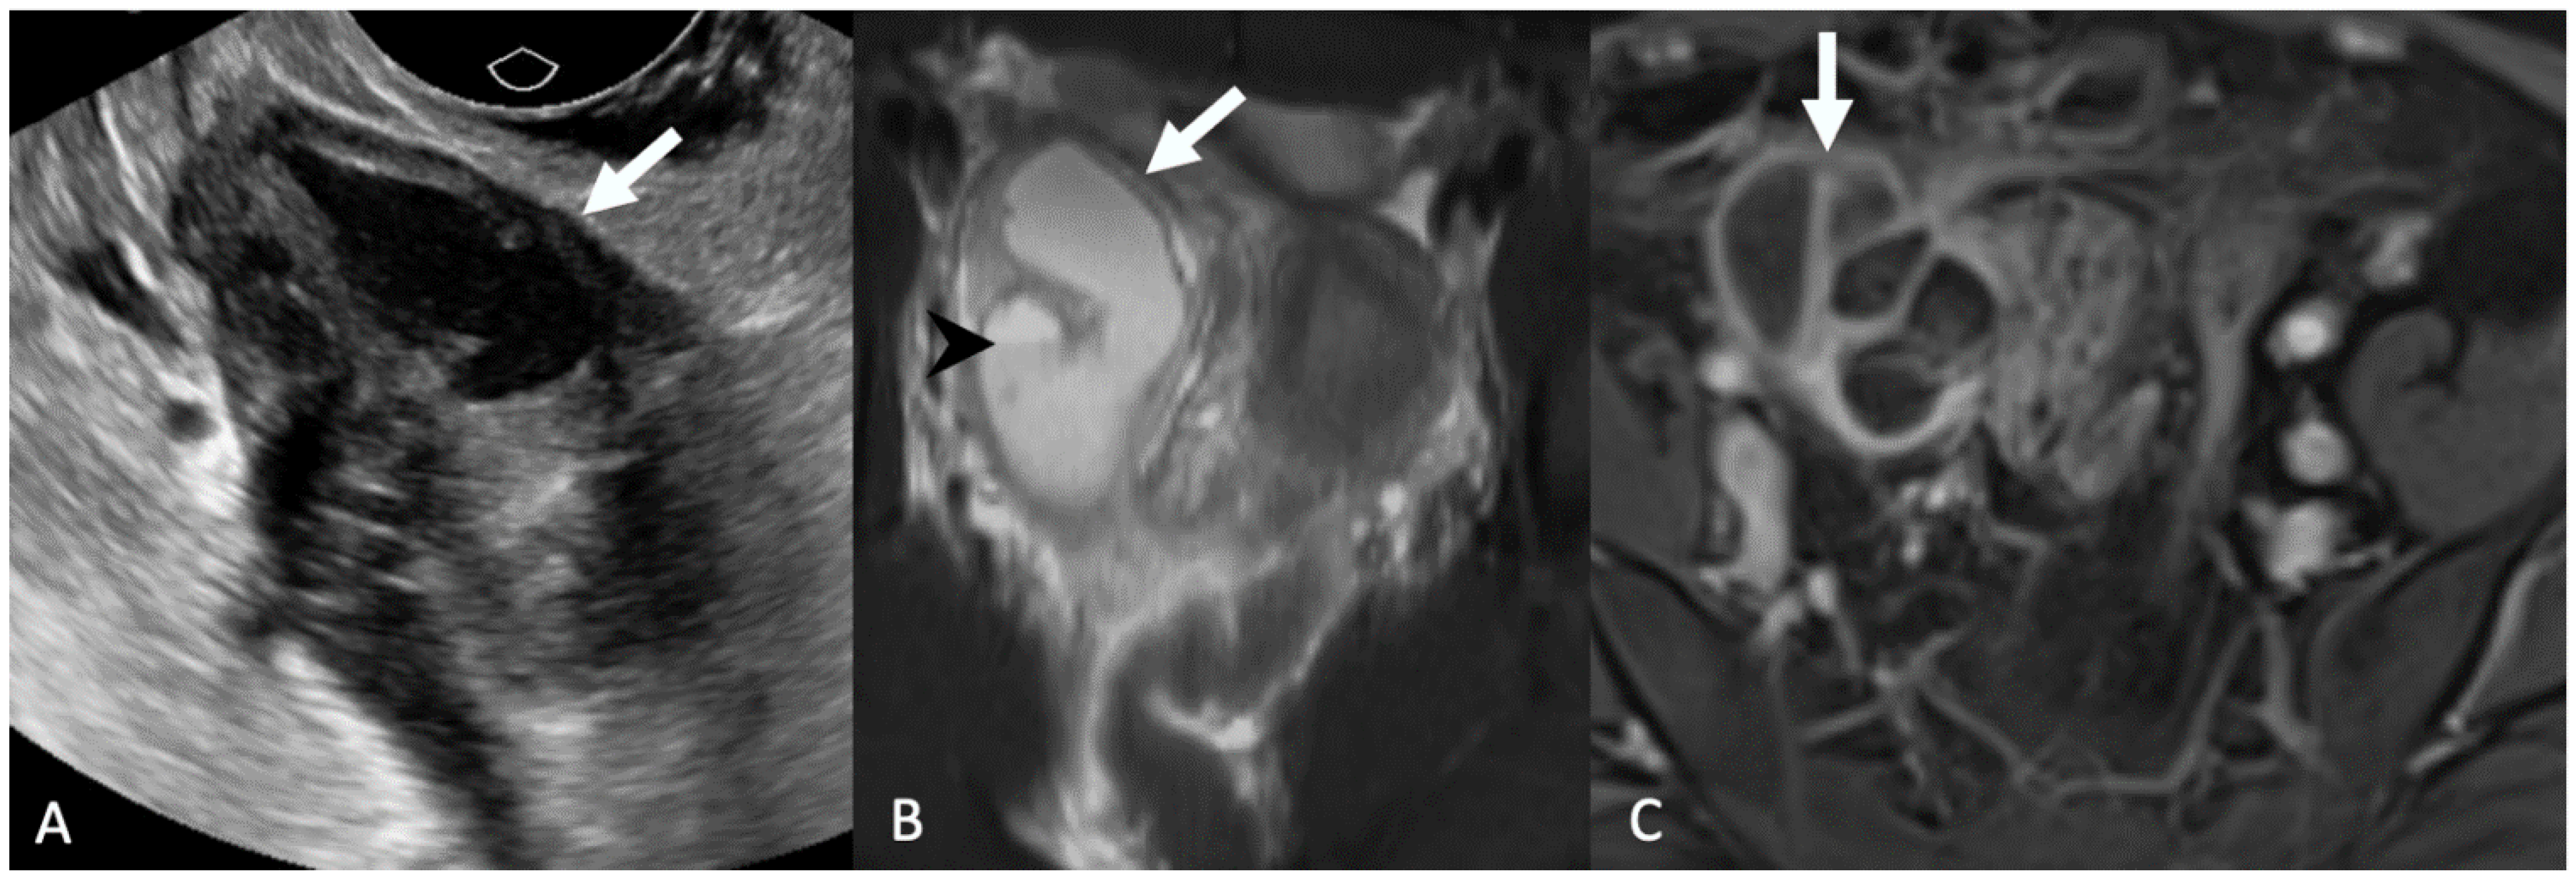

5.1.3. Adnexal Ectopic Pregnancy

5.1.4. Adnexal Torsion